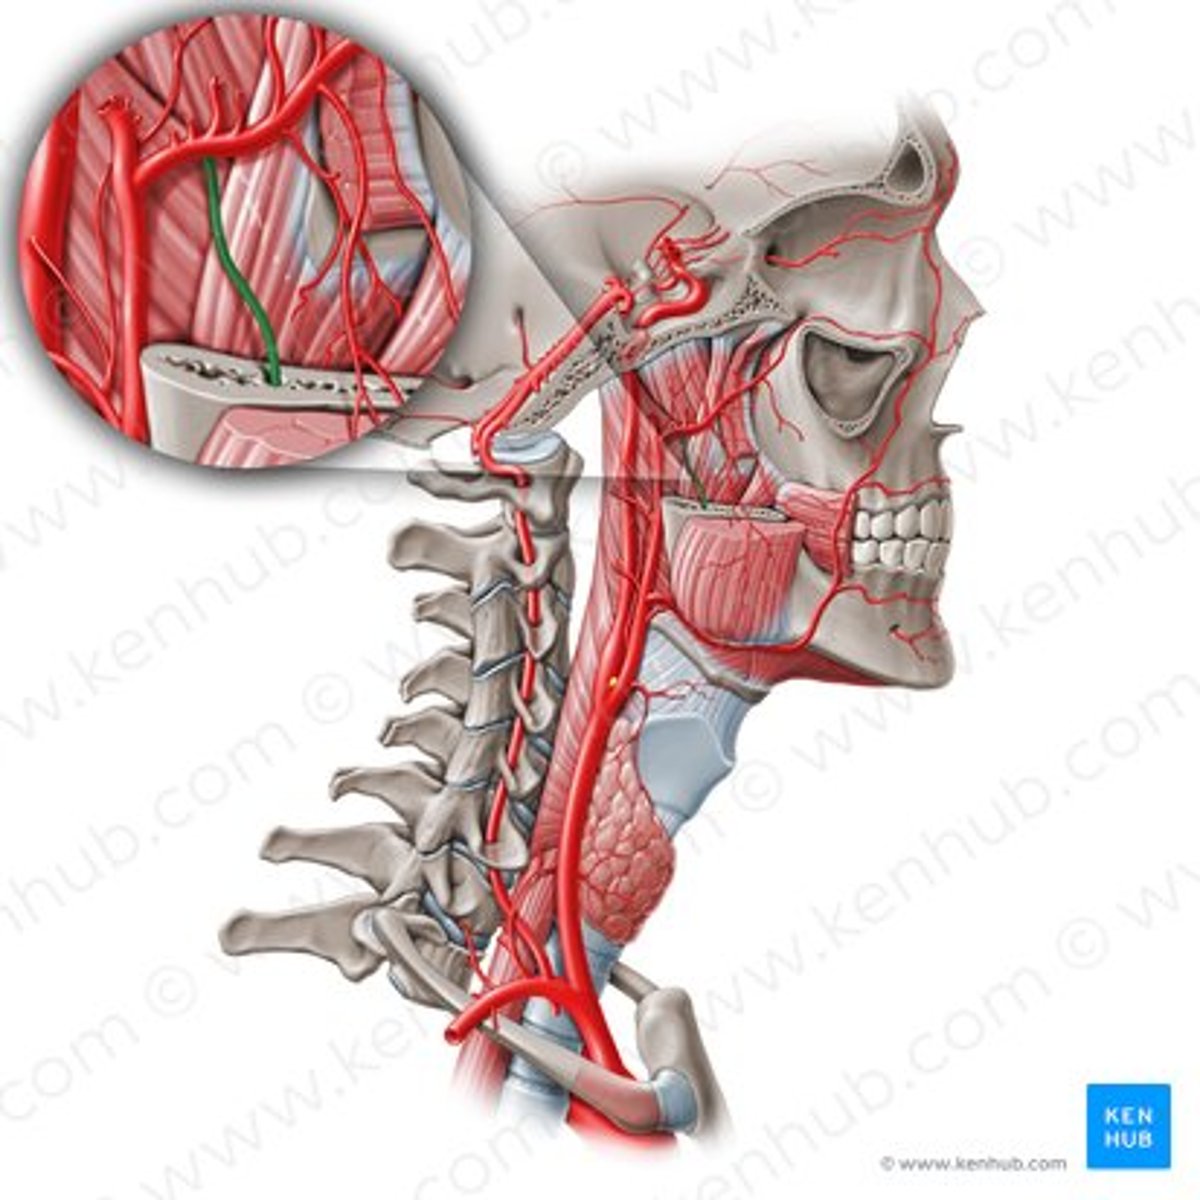

internal carotid artery

lingual artery

lingual artery

inferior alveolar artery

buccal artery